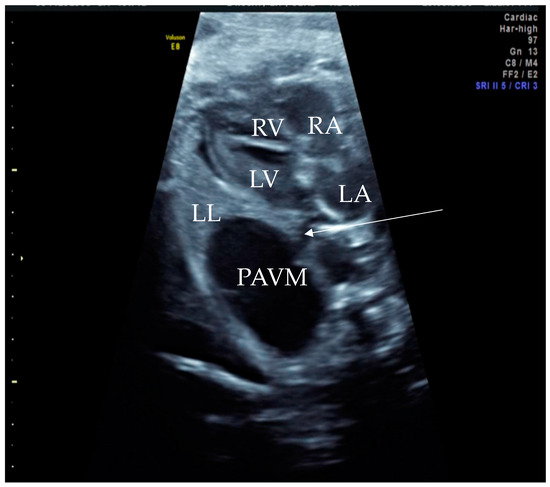

Figure 1. Prenatal B-Mode transabdominal ultrasound picture with cystic structure on the level of four chamber view with a clear linkage of the structure to the left atrium. RV—right ventricle, LV—left ventricle, RA—right atrium, LA—left atrium, LL—left lung, PAVM—pulmonary arteriovenous malformation, arrow—showing the connecting vessel to the left atrium and the PAVM. Actually, this finding led to the suspicion of PAVM. We needed to prove it with color Doppler, as shown in the next picture.